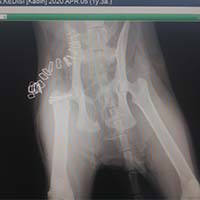

Yalıkavak veteriner kliniğimizde gerçekleştirdiğimiz ortopedik cerrahi uygulamalar:

Ortopedik cerrahi oldukça titizlik ve özen gerektiren cerrahi uygulamalardır. Diğer cerrahi disiplinlere nazaran asepsi ve antisepsi (sterilizasyon) konusunda ASLA hata kabul etmez. Eğer bu aşamada özensiz davranılırsa, postoperatif süreçte kemik dokunun iltihaplanmasına neden olup, kemiklerin kaynaması gecikmiş olur.